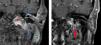

A cerebral magnetic resonance imaging (MRI) was performed, with images suggestive of left MEO, inflammatory changes in the middle ear and deep cervical spaces, and a small abscess in the chewing space, osteomyelitis in the left clivus and left occipital condyle (Fig. 1A).

(A) Coronal T1 sequence, gadolinium. Thickening of the left external auditory canal (blue star) and soft tissues (orange star), parotid gland (green star), temporomandibular joint (straight arrow), occipital condyle (red star) and middle ear (curved arrow)]. (B) Similar section after 18m. Clear improvement, with disappearance of the occupation of the middle ear and decrease in the volume of the tissues originally affected. Unspecific enhancement at the jugular foramen (red arrow).

A myringotomy and transtympanic drainage in left ear were performed, obtaining retrotympanic mucus. After the procedure, the patient's hearing loss was reversed, and there was complete resolution of the temporal headache. The patient recovered after 6 months of treatment with voriconazole and without the need for surgical debridement. The study was completed 18 months after diagnosis using MRI (Fig. 1B), which showed that the middle ear was no longer occupied and that there was no enhancement of the originally affected tissues.